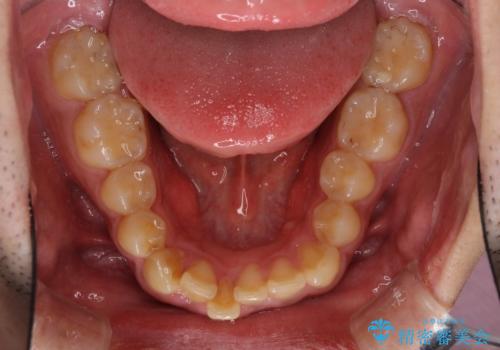

- 上下前歯のデコボコと下の前歯が隠れるほどの深い咬み合わせを気にして来院された患者様です。

インビザラインによる上下歯列の拡大と、IPR(歯と歯の間を削る)にるスペースの獲得により、口元のデコボコとディープバイトを改善することとしました。

デコボコがなくなったことで日頃の清掃が行いやすくなり、深い咬み合わせが改善したことで、食いしばりによる顎の負担も軽減されました。